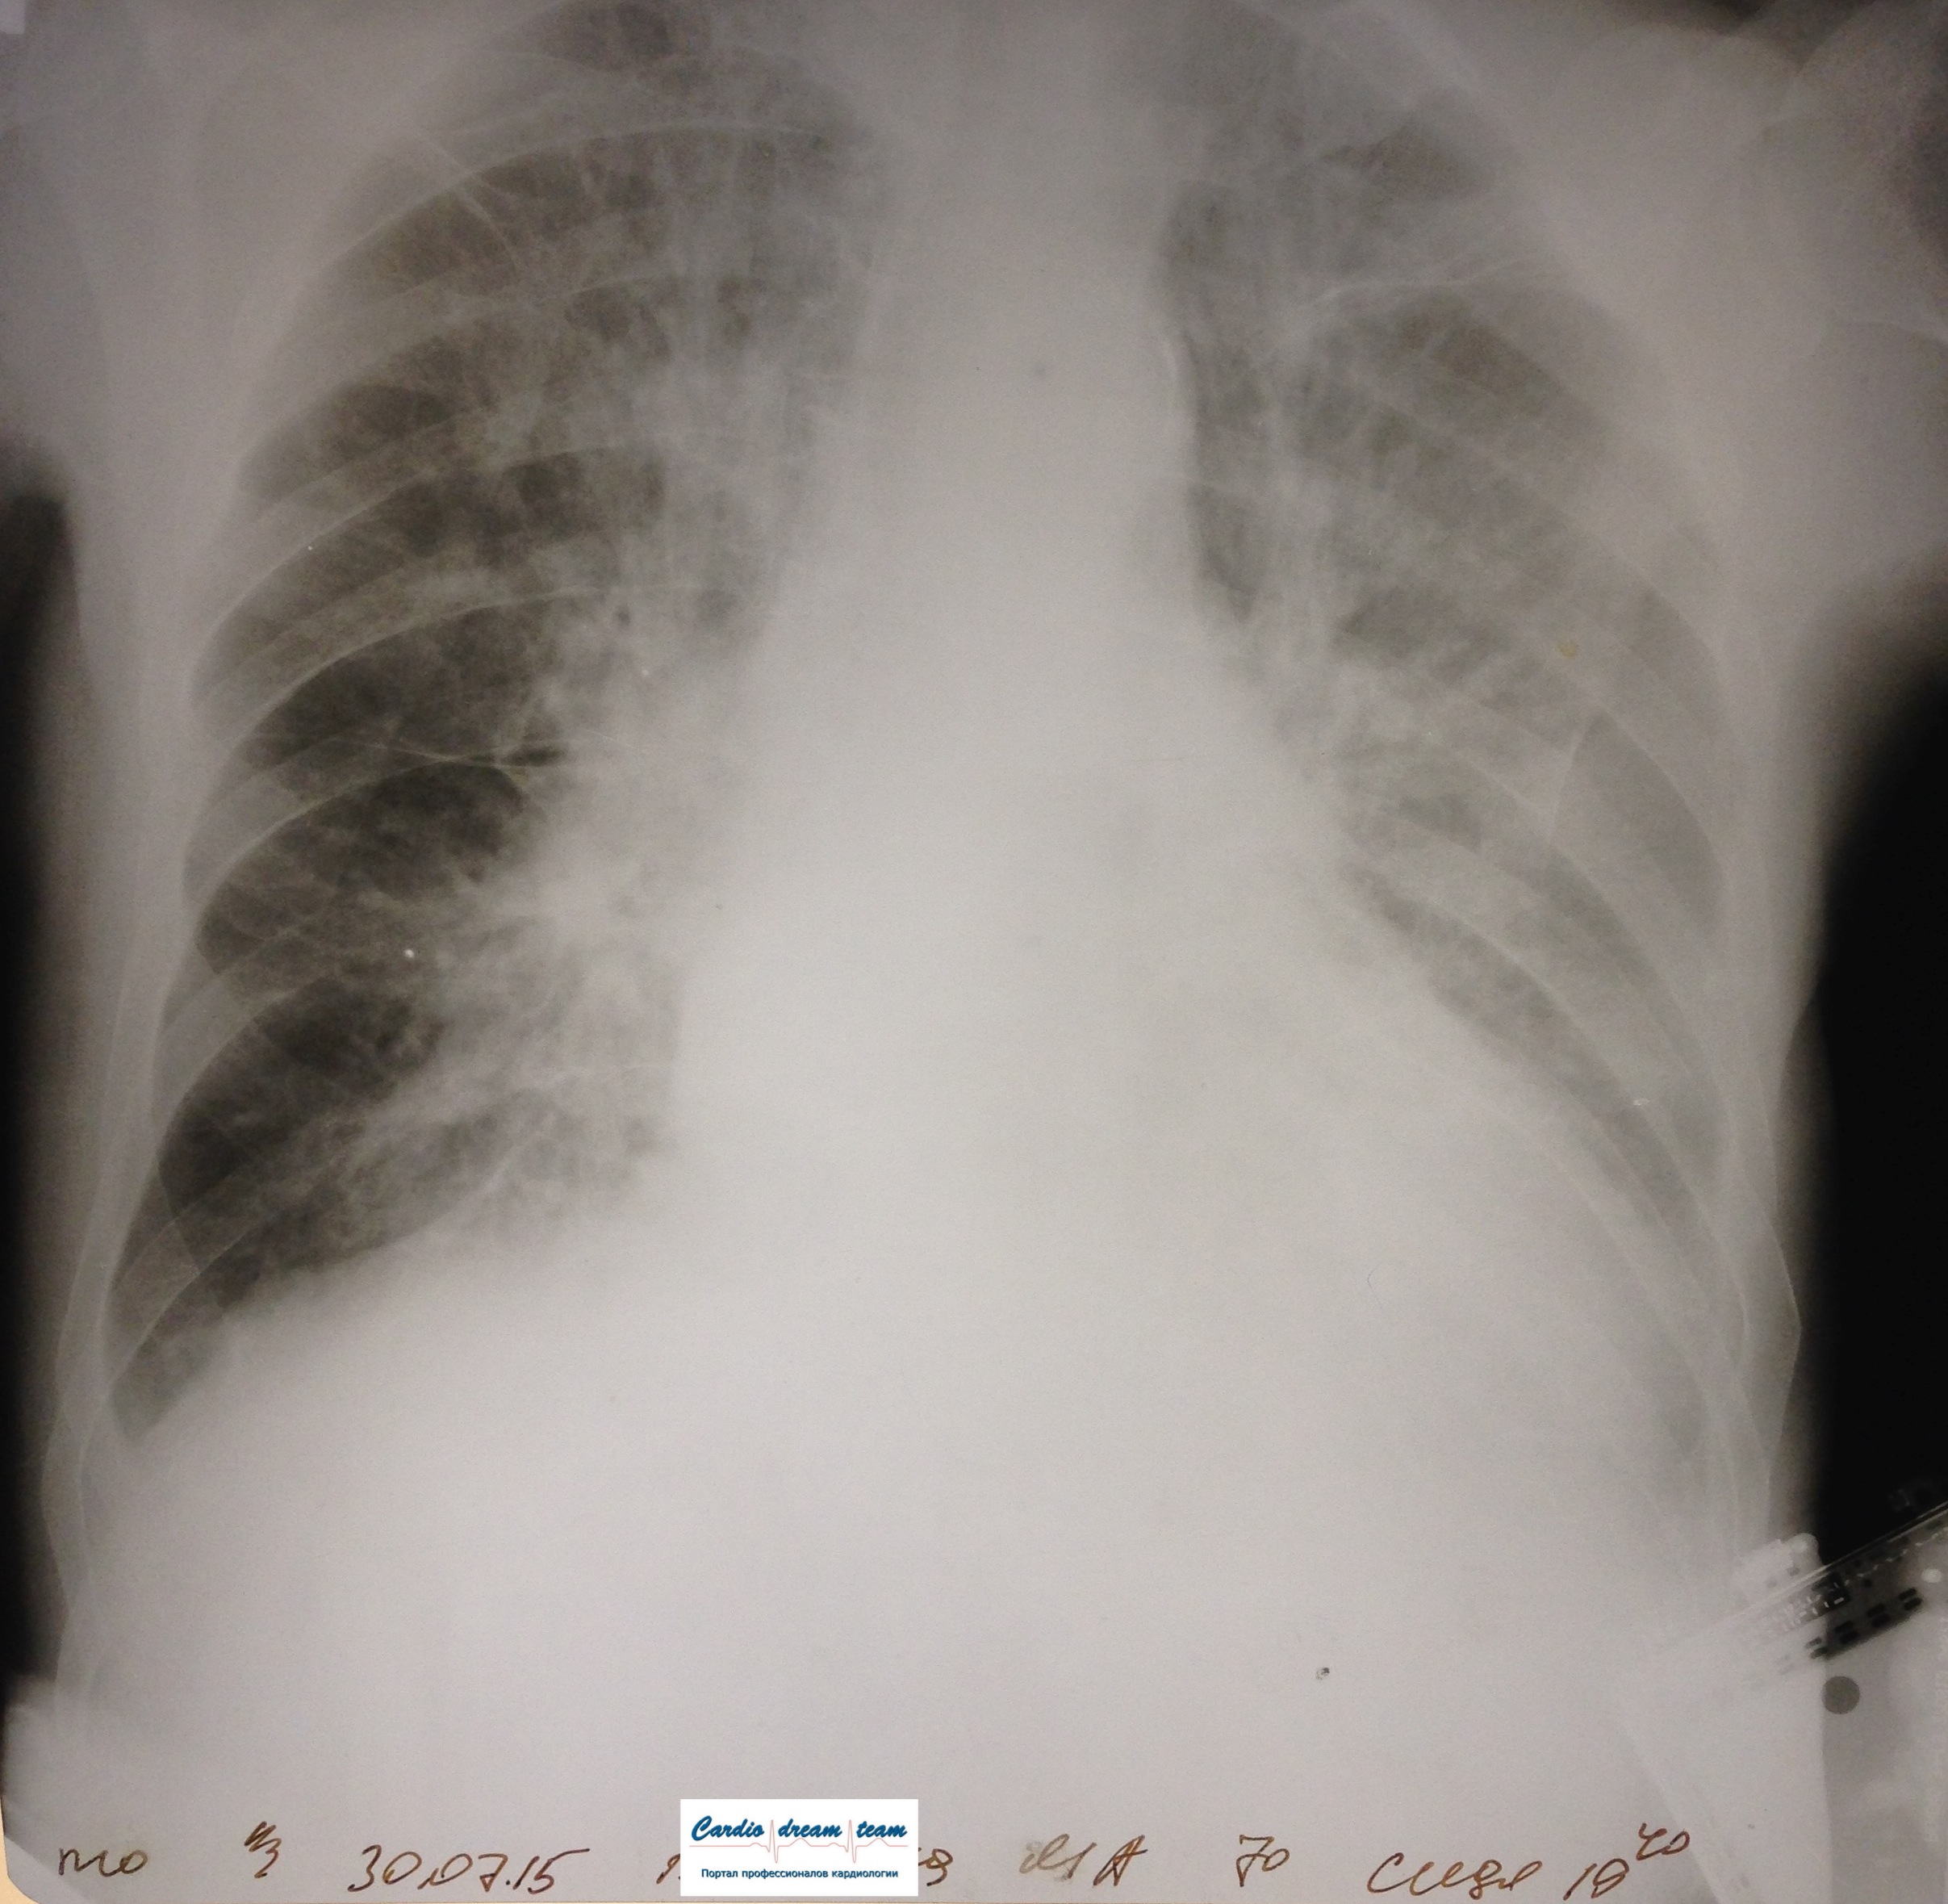

Пневмонии нет.